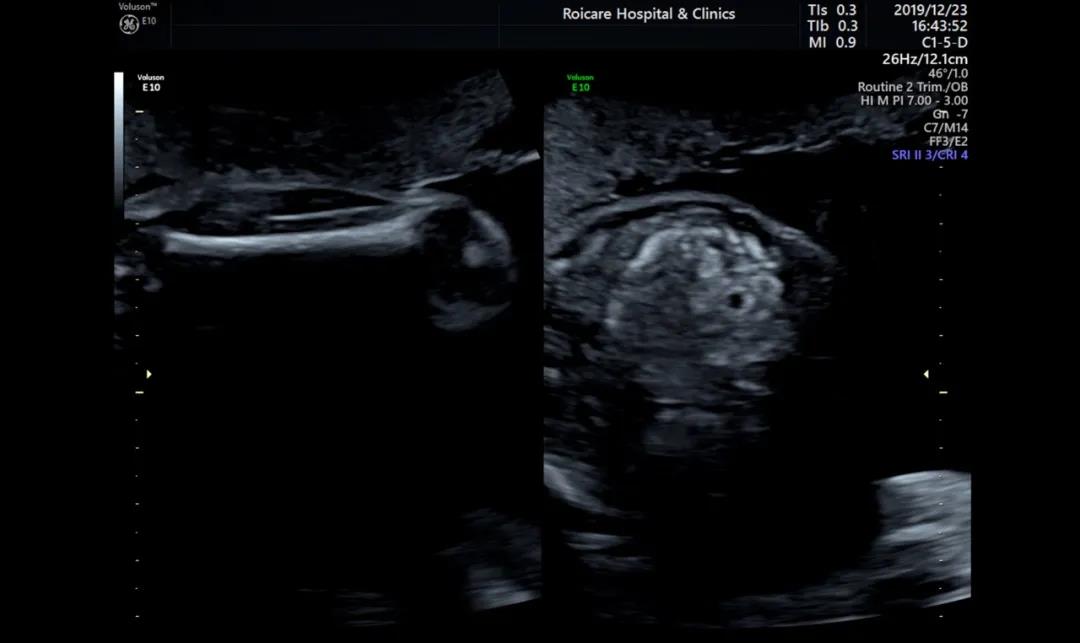

4.肾脏皮质回声增强

肾脏皮质回声增强往往是多囊肾、肾发育不良、一些综合征的表现(Meckel-Gruber综合征)、染色体异常等疾病的一种表现。当看到肾皮质强回声时,需要专业的产前诊断医生给您进一步建议,包括我们产前诊断羊水穿刺,甚至需要家族做泌尿系超声检查,协助一些遗传性疾病的诊断。

那是不是肾皮质强回声的胎儿都不能要了?当然不是,有一些正常肾脏发育中也存在这样变异,同时某些肾脏的问题预后也是比较好的,所以宝妈们不要轻易地放弃,也不要盲目的赌博。来产前诊断门诊,让专业的产前诊断医生给您专业的解释和评估。